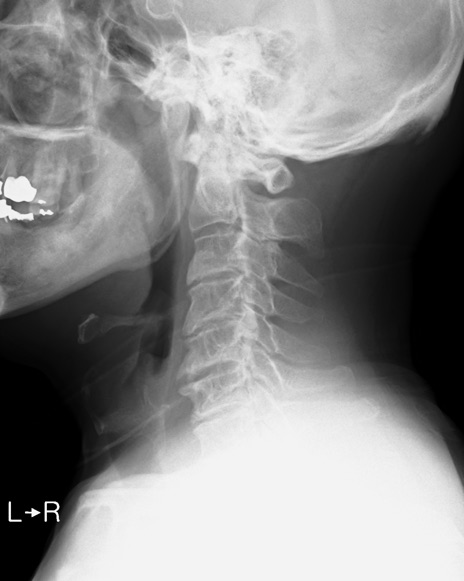

【整形】TIPS症例7 頚椎レントゲン(側面像)

頚椎レントゲン

側面像(伸展)